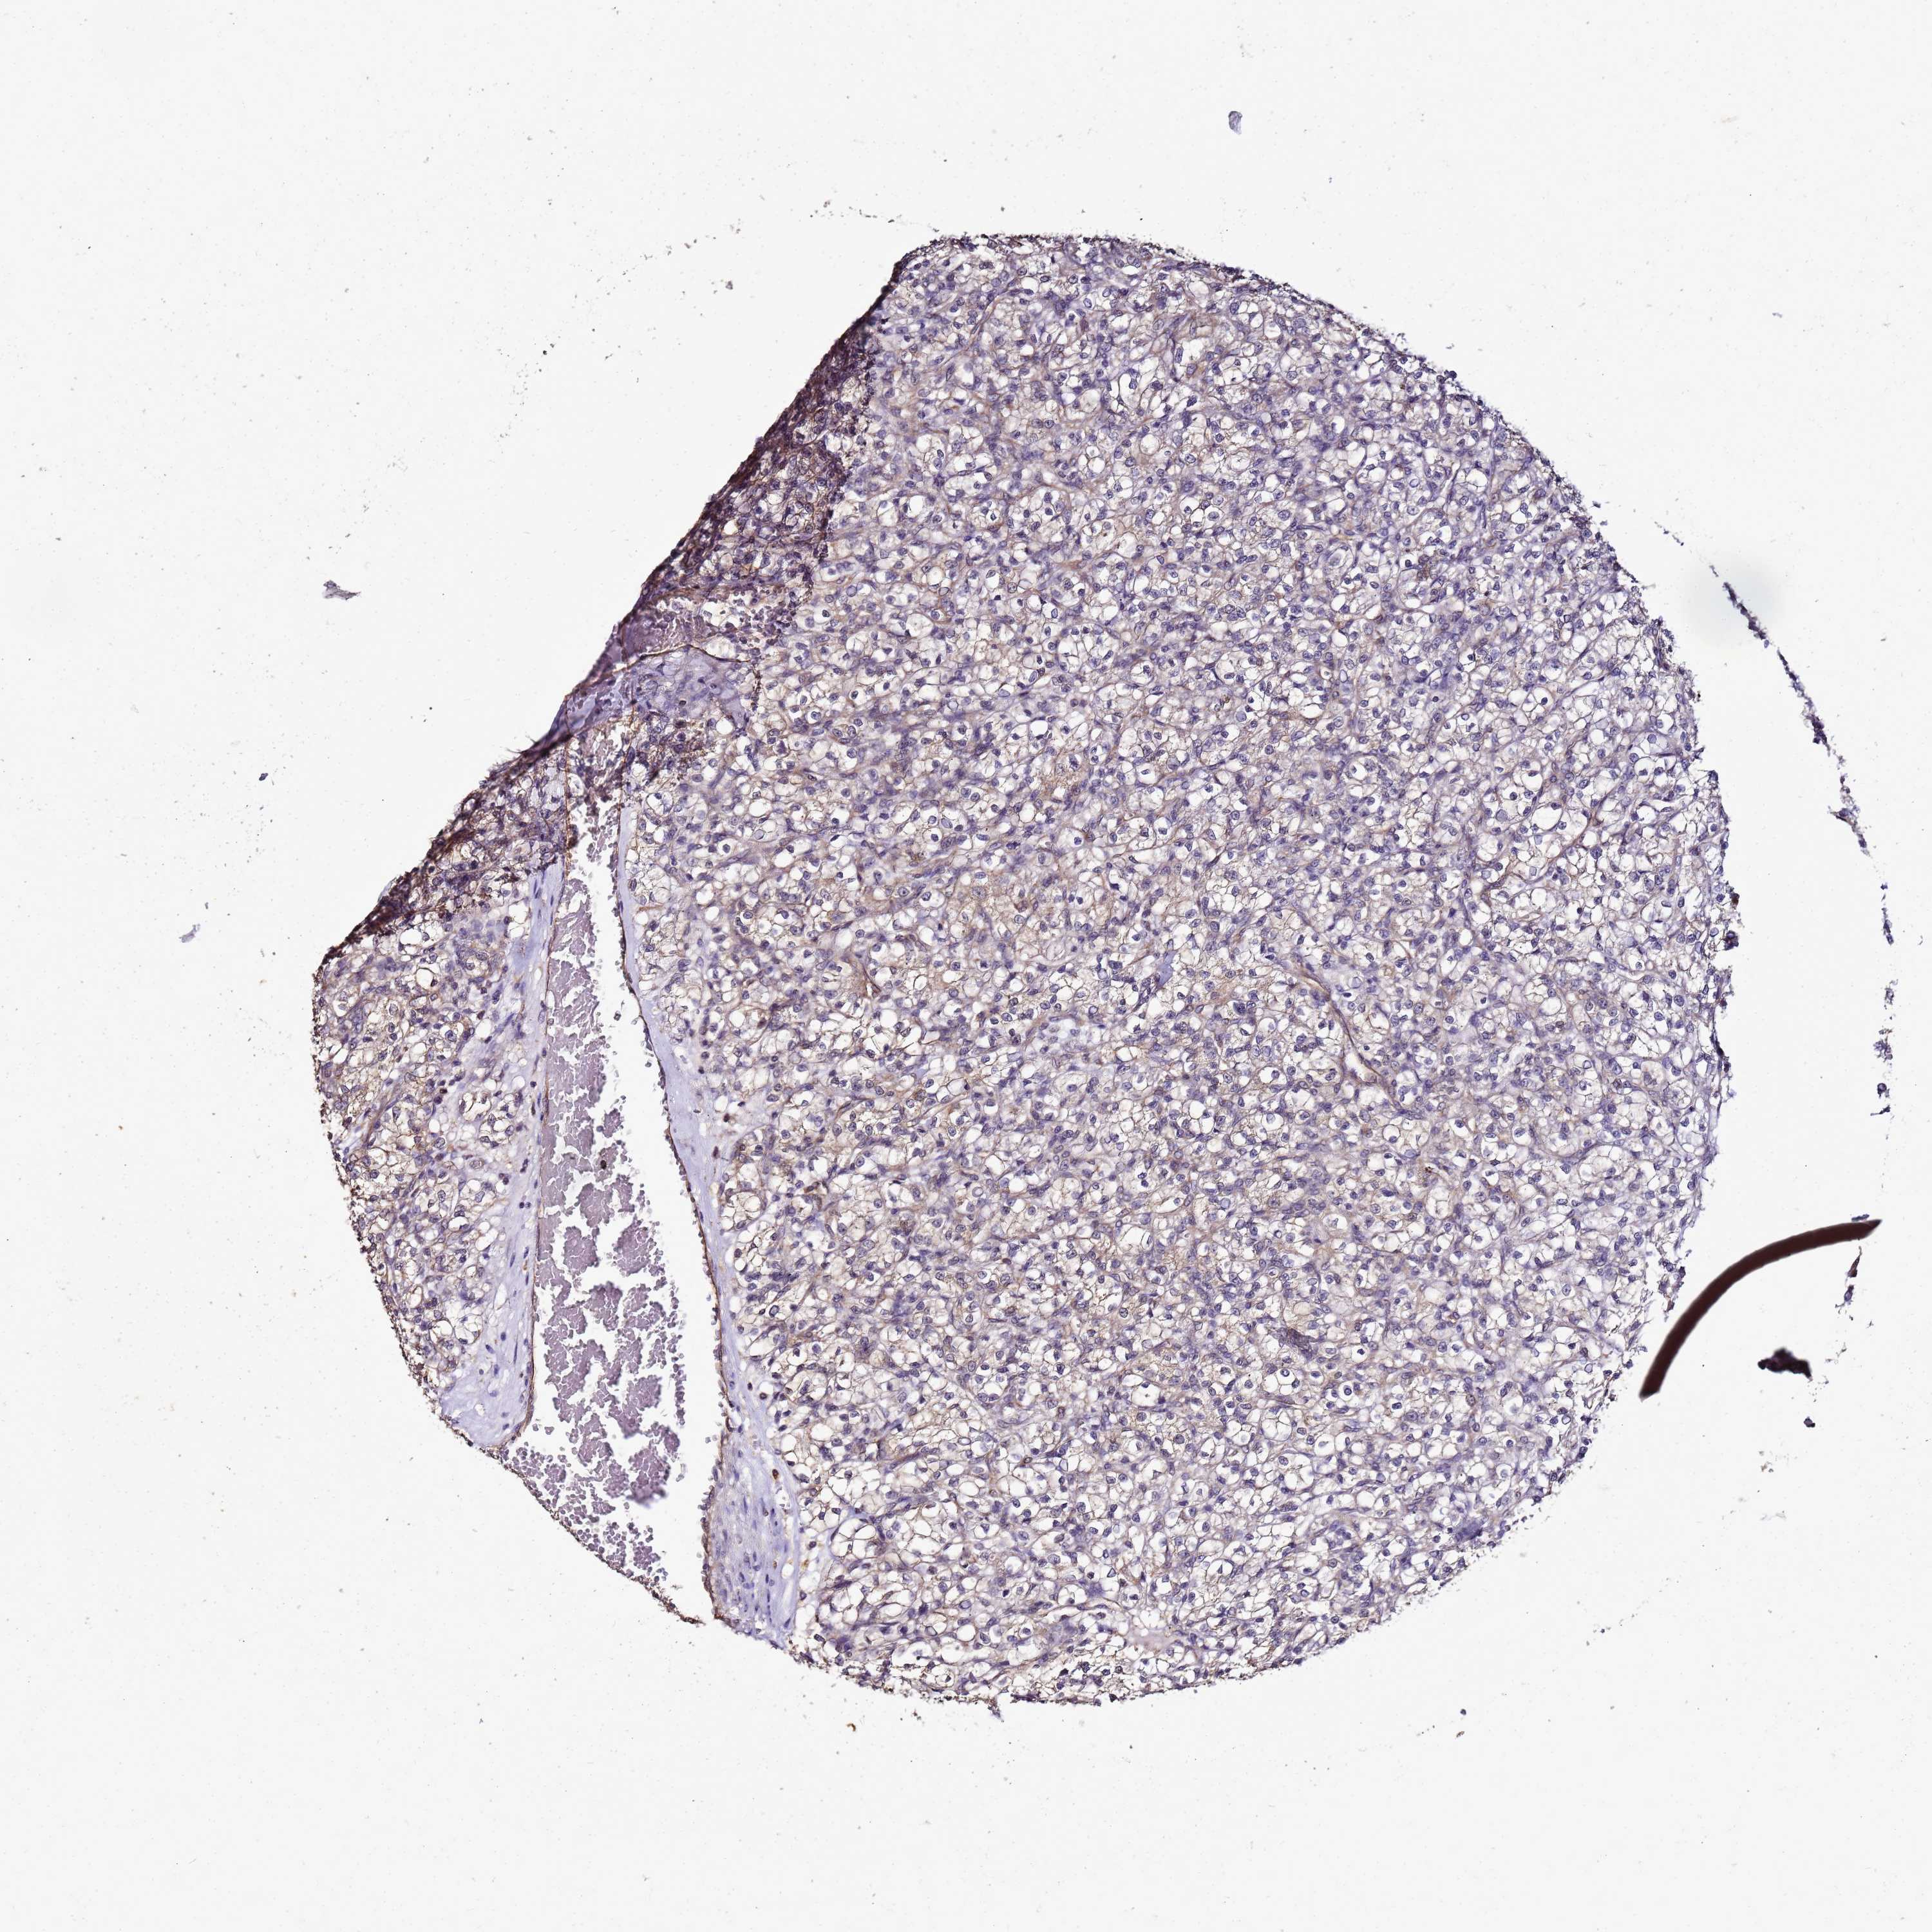

KIDNEY RENAL CLEAR CELL CARCINOMA (VALIDATION) - Interactive survival scatter ploti

The Survival Scatter plot shows the clinical status (i.e. dead or alive) for all individuals in the patient cohort, based on the same data that underlies the corresponding Kaplan-Meier plots. Patients that are alive at last time for follow-up are shown in blue and patients who have died during the study are shown in red.

The x-axis shows the expression levels (FPKM) of the investigated gene in the tumor tissue at the time of diagnosis. The y-axis shows the follow-up time after diagnosis (years). Both axes are complimented with kernel density curves demonstrating the data density over the axes. The top density plot shows the expression levels (FPKM) distribution among dead (red) and alive patients (blue). The right density plot shows the data density of the survived years of dead patients with high and low expression levels respectively, stratified using the cutoff indicated by the vertical dashed line through the Survival Scatter plot. This cutoff is automatically defined based on the FPKM cutoff that minimizes the p-score. The cutoff can be changed by dragging the vertical line or by entering a cutoff value in the square labeled "Current cut-off".

Under the Survival Scatter plot the p-score landscape (black curve; left axis) is shown together with dead median separation (red curve; right axis). Dead median separation is the difference in median mRNA expression between patients who have died with high and low expression, respectively. It is calculated as follows: median FPKM expression of dead patients with high expression - median FPKM expression of dead patients with low expression. This is intended to aid the user in visually exploring custom cutoffs and the associated p-scores and dead median separation.

Individual patient data is displayed and can be filtered by clicking on one or more of the category buttons on the top of the page. Categories describing expression level and patient information include: high, low, alive, dead, female, male and tumor stages. The scale of the x-axis can be toggled between linear and log-scale by clicking on the "x log" button. Mouse-over function shows TCGA ID, patient information and mRNA expression (FPKM) for each patient.

& Survival analysisi

Kaplan-Meier plots summarize results from analysis of correlation between mRNA expression level and patient survival. Patients were divided based on level of expression into one of the two groups "low" (under cut off) or "high" (over cut off). X-axis shows time for survival (years) and y-axis shows the probability of survival, where 1.0 corresponds to 100 percent.

ENOPH1 is not prognostic in Kidney Renal Clear Cell Carcinoma (validation)

: 47.23

Average pTPM 39.6

Number of samples 100